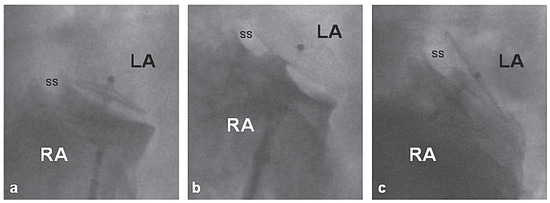

Triple Percutaneous Patent Foramen Ovale Closure

Percutaneous patent foramen ovale (PFO) closure is mainly performed for secondary prevention of presumed paradoxical embolism. Since a residual shunt has been associated with recurrent events, complete PFO closure is desirable. We report the first case of ultimately successful percutaneous PFO closure using [...] Read more.

Percutaneous patent foramen ovale (PFO) closure is mainly performed for secondary prevention of presumed paradoxical embolism. Since a residual shunt has been associated with recurrent events, complete PFO closure is desirable. We report the first case of ultimately successful percutaneous PFO closure using successively 3 Amplatzer PFO devices. Full article